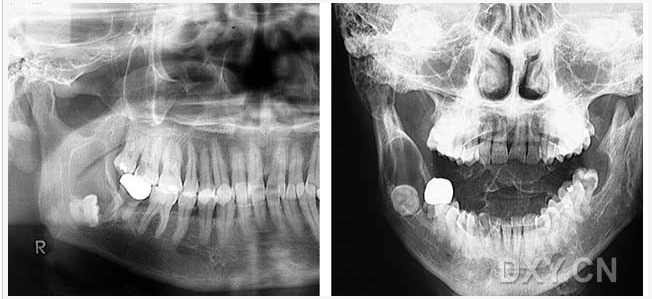

頜骨骨折